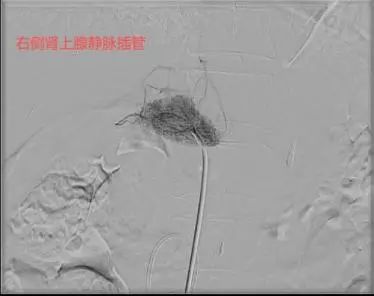

58岁的杨先生患高血压多年,平日里血压控制不佳,近1年来出现血钾减低,间断进行补钾治疗后仍无法将血钾维持在正常范围。于是来到市四医院寻找原因,CT提示左侧肾上腺结节样增生,考虑杨先生存在原发性醛固酮增多症,为了明确双侧肾上腺的优势分泌侧来准确指导外科手术方案。医院介入室团队为患者进行了双侧肾上腺静脉采血术,血检结果提示左侧肾上腺为优势分泌侧。2周后,杨先生在泌尿外科接受了腹腔镜下左侧肾上腺切除术,术后血压恢复正常,无需药物辅助控制。